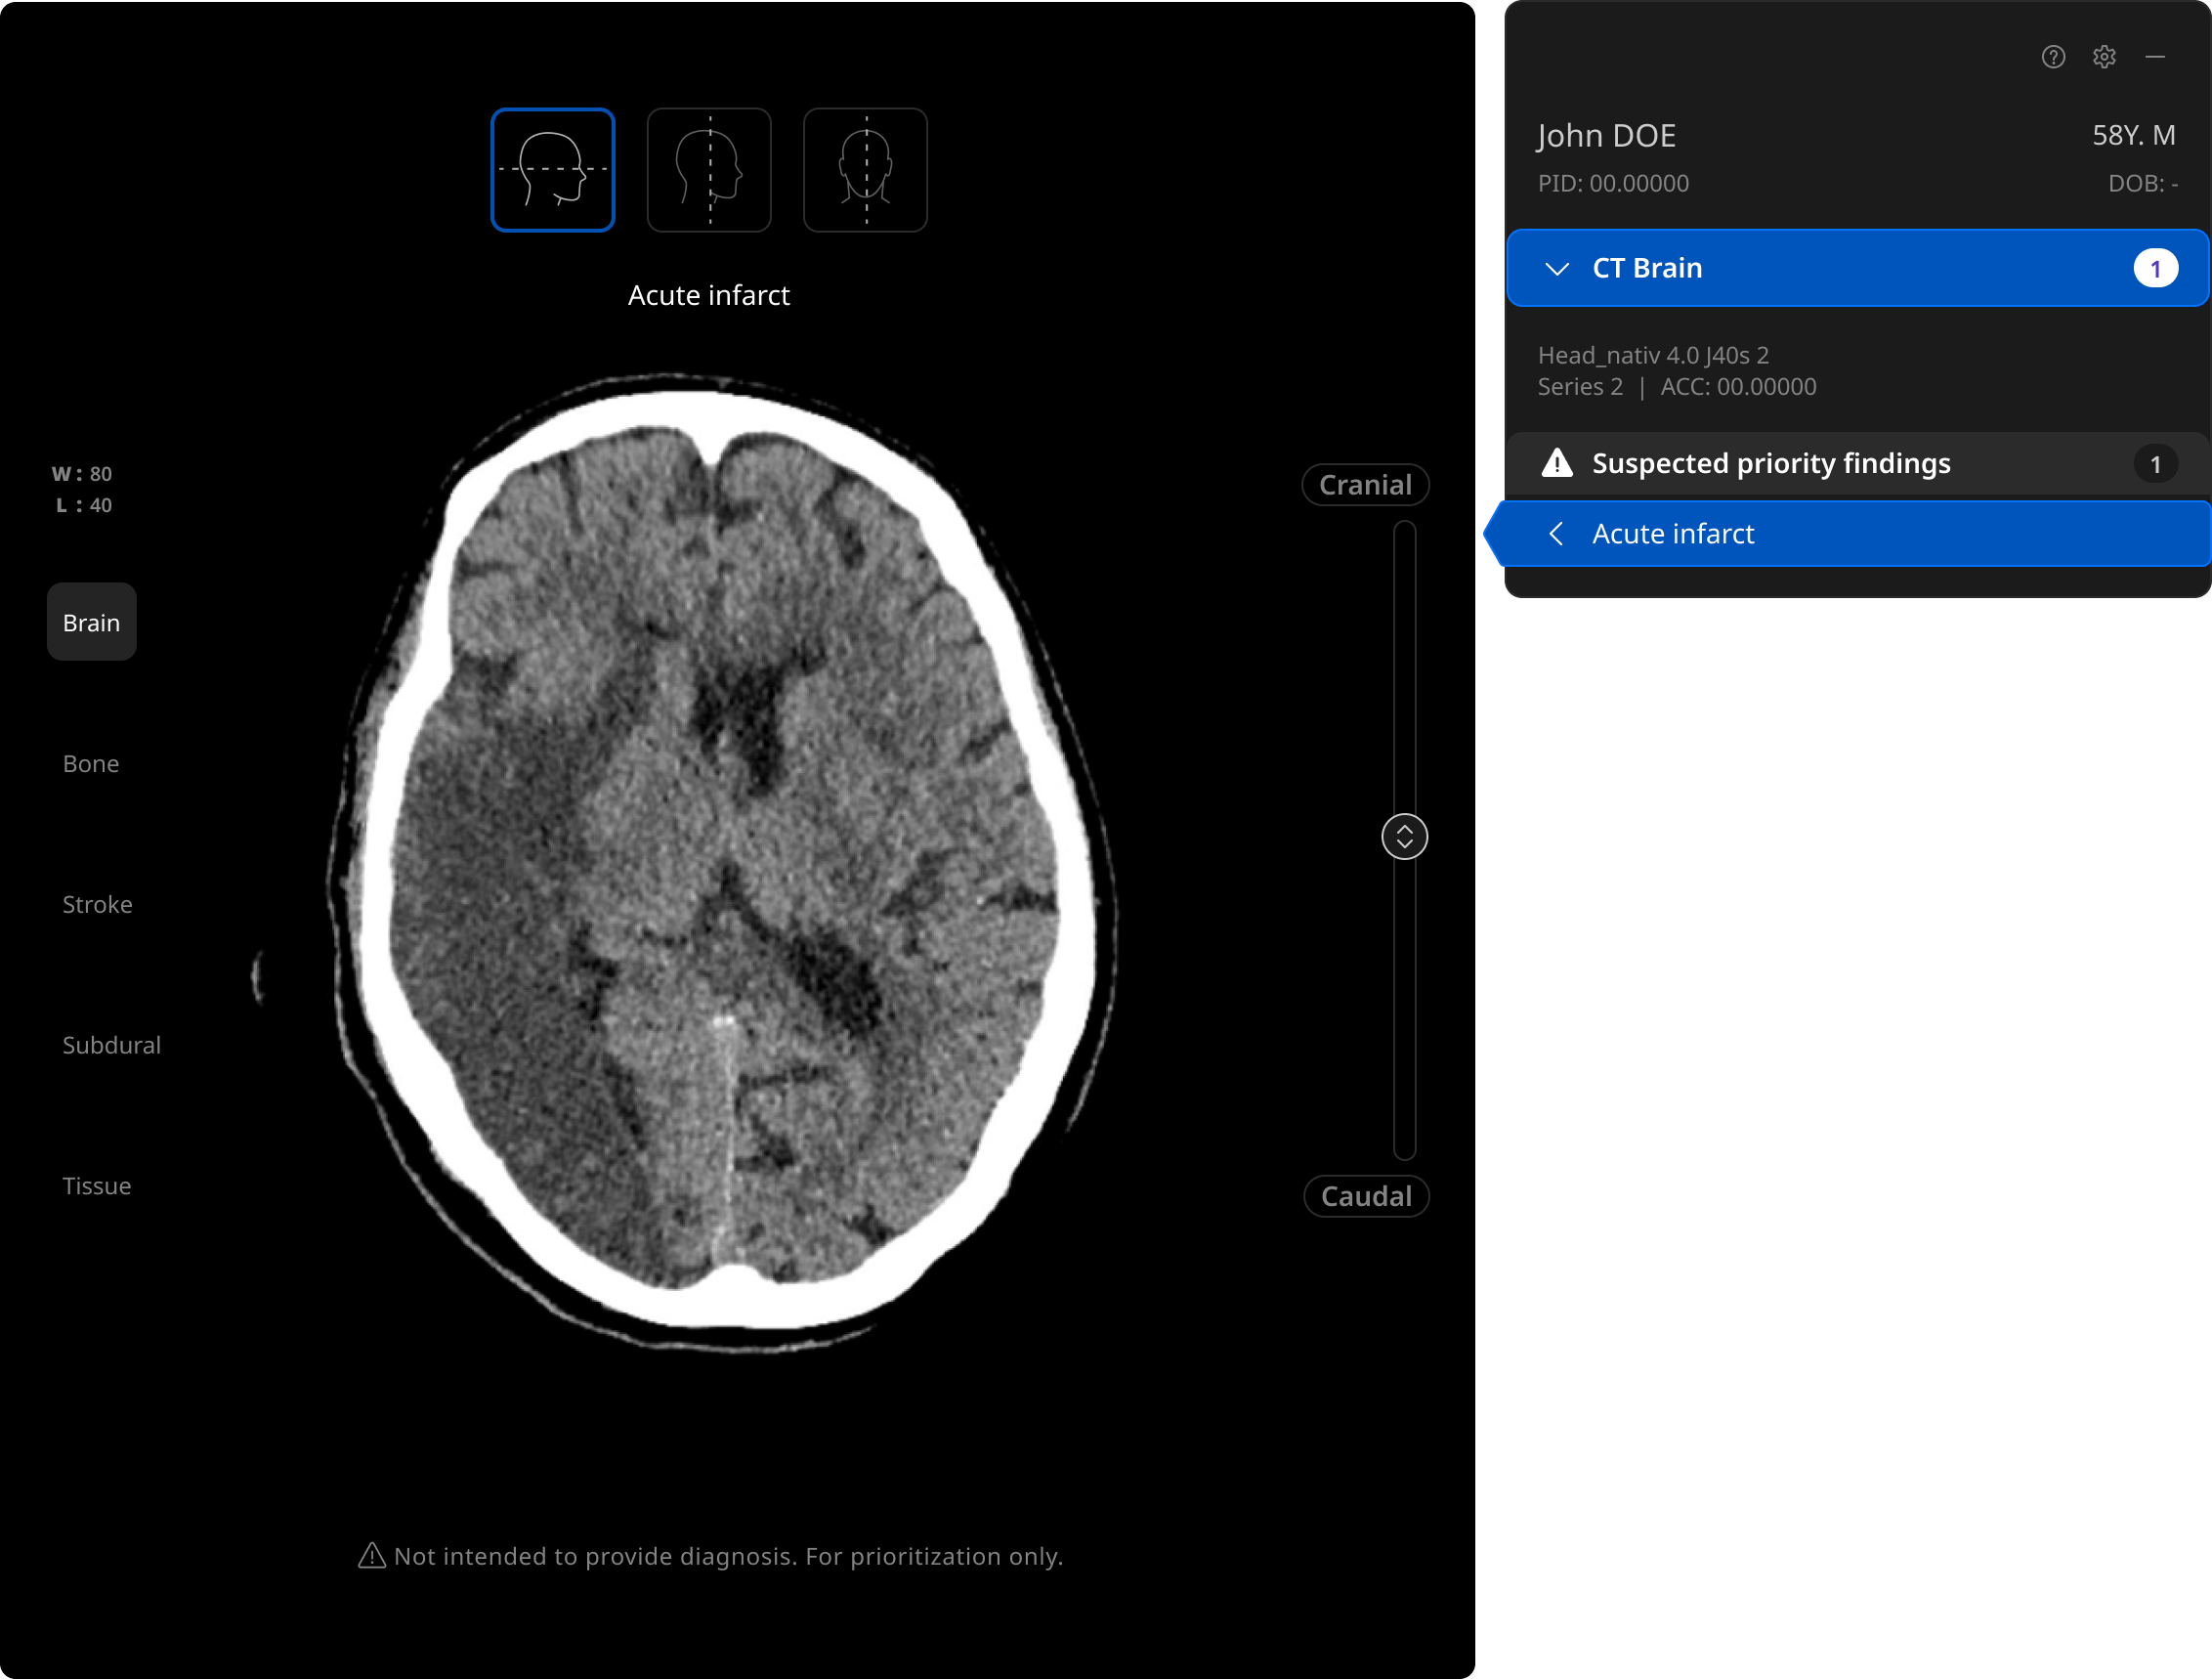

The UI integrates seamlessly with your PACS & RIS, displaying a resizable, no-click overlay window with findings.

Now FDA-cleared: acute infarct triage on non-contrast CT Brain.

Acute infarct is one of the most difficult findings to identify on non-contrast CT. Most ischemic stroke AI triage focuses on large vessel occlusion in one or two vascular territories. The rest go untriaged. Harrison.ai’s triage covers the full geography of the brain. Combined with seven other FDA-cleared CT Brain findings, Harrison.ai delivers the most comprehensive critical exam coverage on non-contrast CT Brain of any AI triage platform. Hemorrhagic and ischemic stroke in one integration.

- Triages actual brain tissue injury as ACA, MCA, PCA, cerebellar, basilar, and watershed infarcts, not just vessel occlusions.

- Up to 89.2% sensitivity on thin slices and 85.7% on thick slices with multiple operating points achieving 80% sensitivity/80% specificity on each.

- Validated against confirmed infarcts on advanced imaging, even when not guaranteed to be visible on non-contrast CT.

- Eligible for analysis on any non-contrast head CT, not just patients on a dedicated stroke protocol.